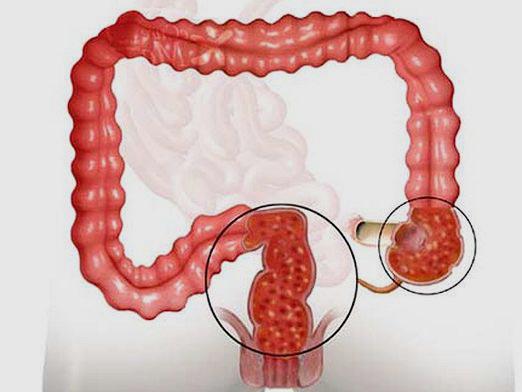

- Онкологические заболевания в области прямой или сигмовидной кишки, приводящие к сужению просвета. Это может сопровождаться изменениями в частоте и форме стула, периодическими поносами и болями в животе.

- Сужение или закрытие просвета кишечника из-за дивертикулита, внутренней грыжи или заворота кишечника. Запоры могут чередоваться с колитами, вздутием живота и наличием крови в кале.

При попытках самостоятельно справиться с запором часто возникает чрезмерное натуживание во время акта дефекации. Это может привести не только к выпадению прямой кишки и образованию грыжи, но и к микроразрывам анального кольца, а также к образованию геморроидальных узлов и шишек.

Какие последствия может иметь такое заболевание в пожилом возрасте, если его не лечить? Затвердевшие каловые массы начинают подвергаться процессам гниения и разложения внутри кишечника. Это приводит к воспалению слизистой оболочки кишечника, что может вызвать хронические колиты. В результате происходит интоксикация организма, а также ухудшается усвоение витамина В.

Несвоевременное избавление от застоявшихся каловых масс может привести к серьезным осложнениям. Возможные последствия включают:

- Трещины в области ануса. Если запор не лечить, могут возникать новые разрывы и воспаления уже существующих повреждений.

- Геморрой. Это заболевание часто сопровождает хронические запоры, создавая множество неприятных и болезненных ощущений на протяжении всего дня.

- Онкологические заболевания. Такие болезни представляют собой наихудший сценарий развития ситуации.